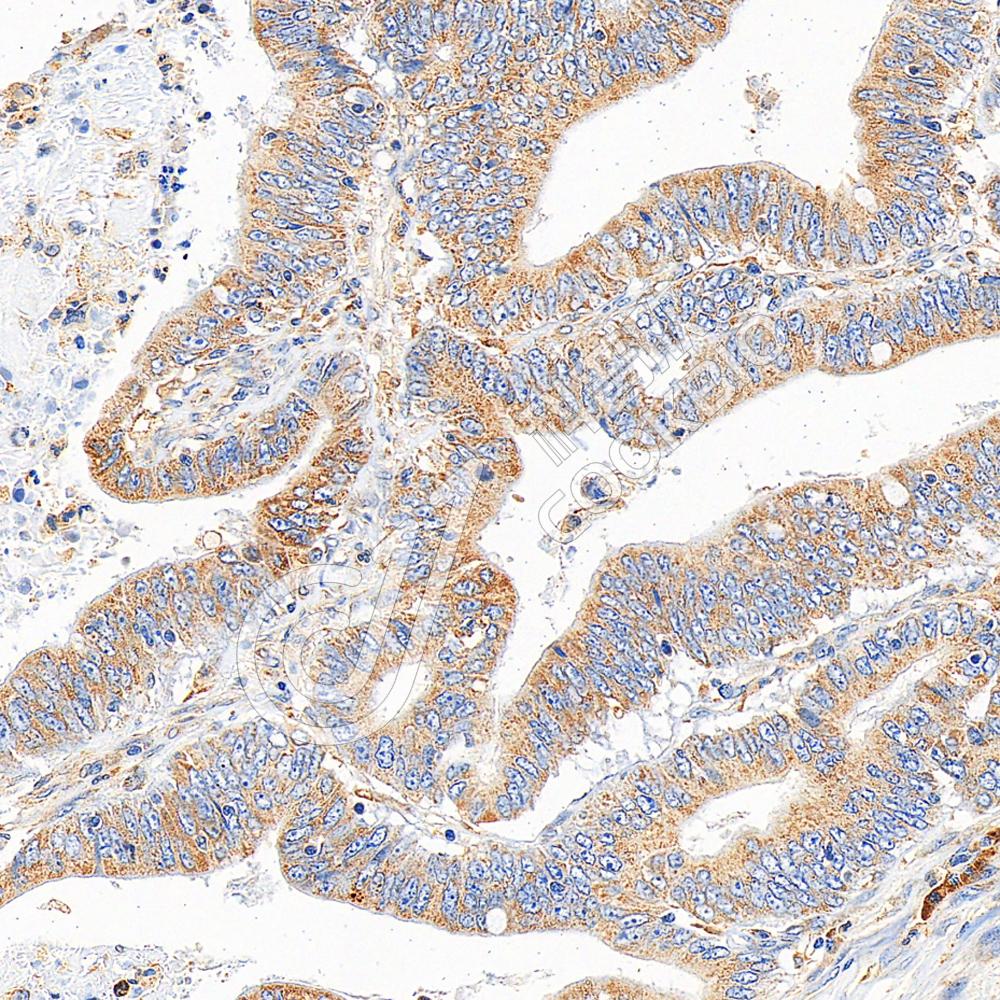

IHC检测MyD88蛋白(货号 K133807).

样品: 小鼠lps(24h)诱导肾脏炎症模型, 4%多聚甲醛 (货号KSG1101) 固定12-24小时.

抗原修复: 柠檬酸抗原修复液(干粉, pH 6.0) (KSG1201), 98℃, 20分钟.

—抗: 1: 300稀释, 4℃ 孵育过夜.

二抗: S-vision免疫组化多聚二抗(山羊抗兔),即用型 (货号KB3906), 室温孵育20分钟.

样品: 大鼠lps(24h)肺诱导炎症模型, 4%多聚甲醛 (货号KSG1101) 固定12-24小时.